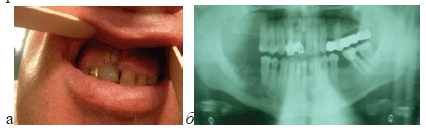

Больной Г. 53 года, мужского пола, обратился с жа-лобой на постоянную боль в области зуба 14. В анамнезе отмечает употребление наркотика “крокодил” (дезоморфин) в течение 18 месяцев. Последний раз употреблял 20 дней назад до операции. 10 дней назад оперировался по поводу остеонекроза нижней челюсти (рис.5а).

Рис. 5. Больной Г. с остеонекрозом нижней челюсти, применяющий наркотик “крокодил” (дезоморфин), а)область остеонекроза нижней челюсти до операции, б) область зубов 13,14, в) ортопантомограмма-видны резорбция краев лунки зуба 14 больше 1/2 ее высоты, расширение периодонтальной щели зуба 14, г) рана после удаления зуба 14, д) рана после резекции лунки зуба 14, е) рана после закрытия узловыми швами.

Произведена операция удаления зуба 14 по 2-ому варианту. Под местным обезболиванием удален зуб 14 (рис.5г), образован слизисто-надкостничный лоскут, оголена подлежащая кость. Так как была обнаружена резорбция краев лунки зуба 14 до 1/2 ее высоты, то про-ведена полная резекция лунки зуба (рис.5д). После укорочения межзубной перегородки и мобилизации слизистонадкостничного лоскута, рана закрылась наглухо узловыми швами (рис.5е). Рана заживала первичным натяжением, без осложнений. Швы были удалены на 10 день после операции. Через 2 месяца после удаления, на месте операции слизистая оболочка имела нормальную розовую окраску, обнаруживался тонкий рубец и дефект костной ткани альвеолярного отростка. Больной никаких жалоб не предъявлял.